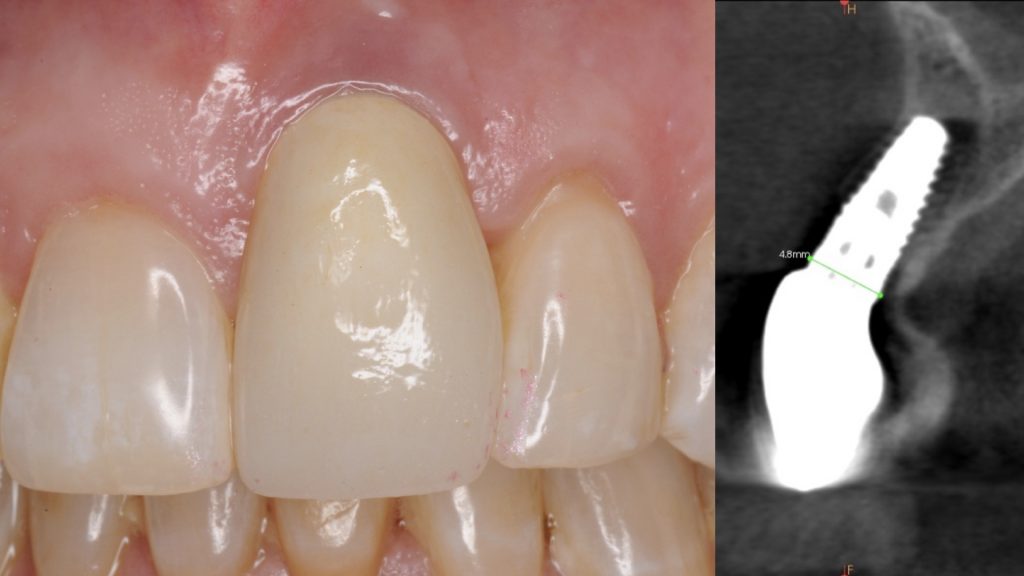

Explantation of an Anterior Implant with Excessive Buccal Inclination and Loss of Tissue

Staged management of a poorly positioned dental implant in the aesthetic zone with compromised results.